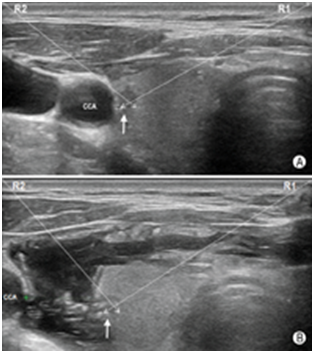

如图19所示,对于气管近旁尤其是2~5点钟位(以甲状腺横切面为参照表盘,于对侧腺体则应是7~10点钟位)的目标结节,穿刺操作宜选用由内向外穿刺法,同时操作者可使用液体隔离技术使目标病灶向外侧移位,增大端侧式穿刺进针的角度,以规避气管壁对穿刺针尖的阻碍,并改善穿刺针尖的显示清晰度。如图20所示,对于位于7~10点位(对侧腺体应是2~5点位)邻近颈总动脉的病灶,也宜选用由"内向外"穿刺法。同样,操作者也可采用液体隔离方法使得颈总动脉向外侧移位,增大目标病灶与颈总动脉之间的距离,避免误伤颈总动脉。

图20液体隔离法增强FNA操作的安全性 A:目标结节(箭头所示)紧邻颈总动脉(CCA),无论是经R1入路还是R2入路,穿刺针伤及颈总动脉的可能性均较大;B:液体隔离后,目标结节(箭头所示)与颈总动脉(CCA)间距增大,穿刺针可安全规避颈总动脉